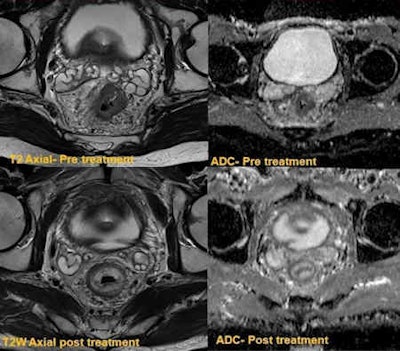

"Peri-tumor fibrosis, desmoplastic reaction, edema, inflammation occur following combined chemoradiotherapy. This poses a considerable diagnostic challenge in restaging because these post-treatment responses can produce spiculated margins and the signal characteristics resemble residual tumor on T2-weighted images. Hence overstaging is potential problem," wrote Jacob, whose co-author was Dr. Muthukumarasamy Balasubramaniam, a specialist registrar at the same institution. "DWI overcomes this pitfall as these changes do not demonstrate restricted diffusion, and the ADC values are generally high, proving to be a useful clinical tool."

Moreover, small residual tumors within the post-treatment changes can also be clearly demonstrated in DWI imaging as these tumors show high signal on high B-value due to restricted diffusion.

Patients who have responded well (complete responders) to initial chemoradiotherapy may be treated under a "wait and watch policy," and in this group of patients, DWI can be used for tumor surveillance, according to the authors. This is becoming an effective alternative for patients who do not want surgery or are not fit for a procedure. Early identification of local recurrence can be salvaged by minor endoscopic resection, avoiding major colorectal surgery.